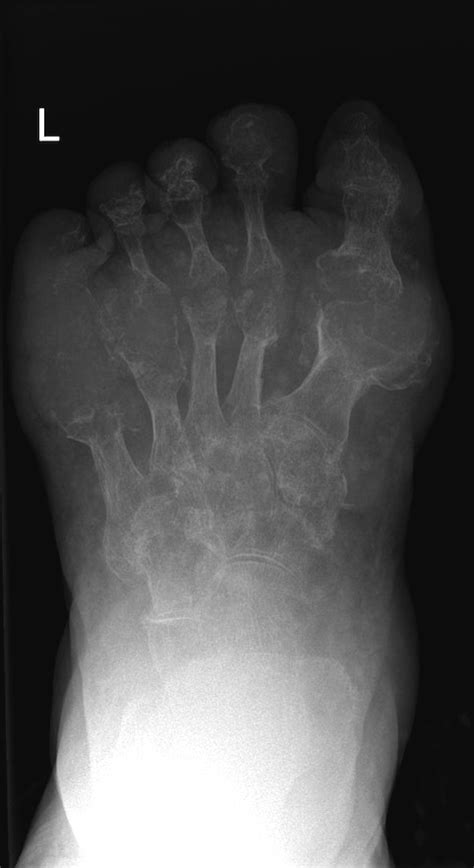

Gout - Radiology At St. Vincent's University Hospital

Gout - Radiology at St. Vincent's University Hospital www.svuhradiology.ie

gout radiology